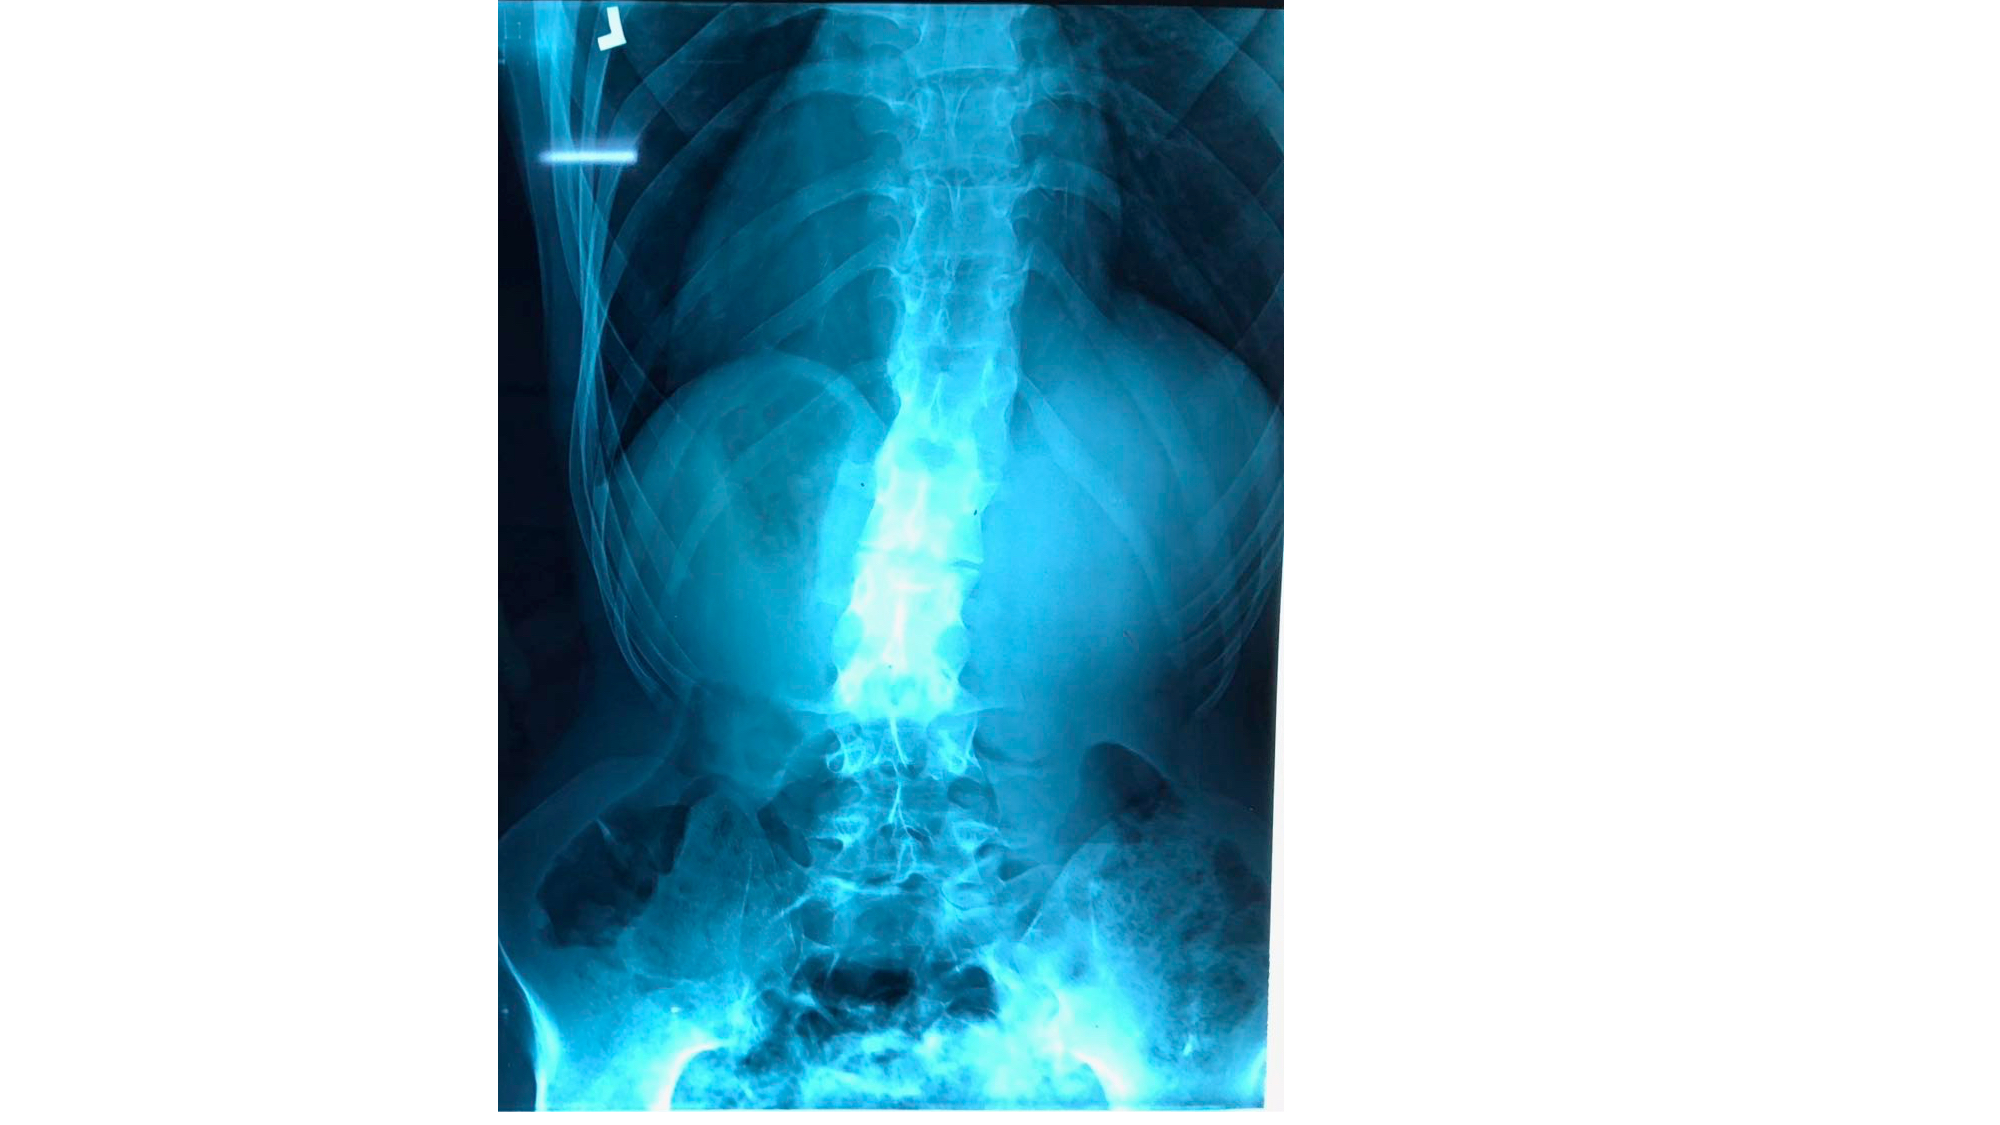

I was also able to meet the first two spine surgery fellows at AaBET. They are both neurosurgeons. The plan after next year is to alternate orthopedic with neurosurgery spine fellows. In addition to their teaching at AaBET, they are mentored by Dr Fasil Mesfin of Univeristy of Missouri, with whom they have weekly cases conferences. They were excited to show me two massive spine tumors they just operated on, one a giant, dumbbell shaped neurofibroma of the lower thoracic spine with bone involvement and preoperative paraparesis; the other a huge aneurysmal bone cyst of posterior lumbar element. Both needed pedicle screw instrumentation and big exposures. I am not a spine surgeon but the operative photos and postop xrays were very impressive.